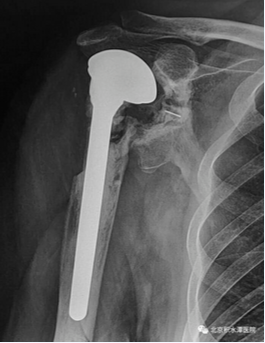

因骨折不愈合、内固定失效,患者在当地行全肩关节置换术,术后10天出现伤口愈合欠佳,渗液较多,经换药、抗炎治疗好转后出院。后反复出现伤口窦道形成,都经换药后愈合,但肩关节功能欠佳。

2018年3月